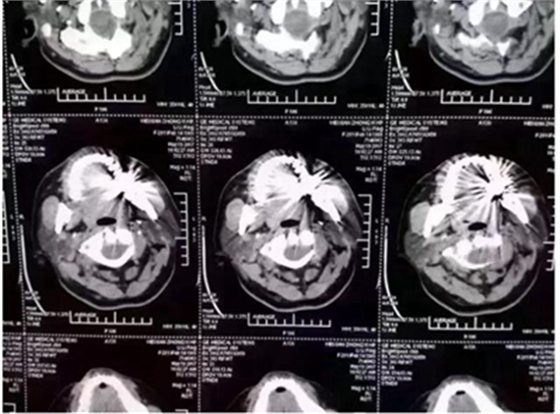

這幾天,一張照片刷爆了牙醫(yī)朋友圈

對這張照片,有牙醫(yī)評論如下:

口內(nèi)有金屬烤瓷牙做核磁共振,CT,以烤瓷牙為中心呈現(xiàn)放射狀影像,無法看清周圍組織,影響臨床診斷,建議條件允許的朋友還是選擇二氧化鋯全瓷冠修復(fù),以免帶來不必要的麻煩!

另外,非金屬的二氧化鋯對X線卻無任何阻擋,只要鑲?cè)攵趸喛敬裳溃蘸笞鲱^顱X線、CT、核磁共振檢查時都不需要拆掉假牙,省去很多麻煩。本文之前曾報道《牙齒阻礙磁共振?那是你沒有用二氧化鋯牙》

2.因金屬內(nèi)冠的存在,透光性、色澤和形態(tài)與自然牙存在較大的區(qū)別,更會在燈光下產(chǎn)生青灰色的效果。同時金屬瓷牙在液體口腔酸堿環(huán)境細菌作用下不穩(wěn)定,患者在做CT核磁共振時金屬有一定的干。